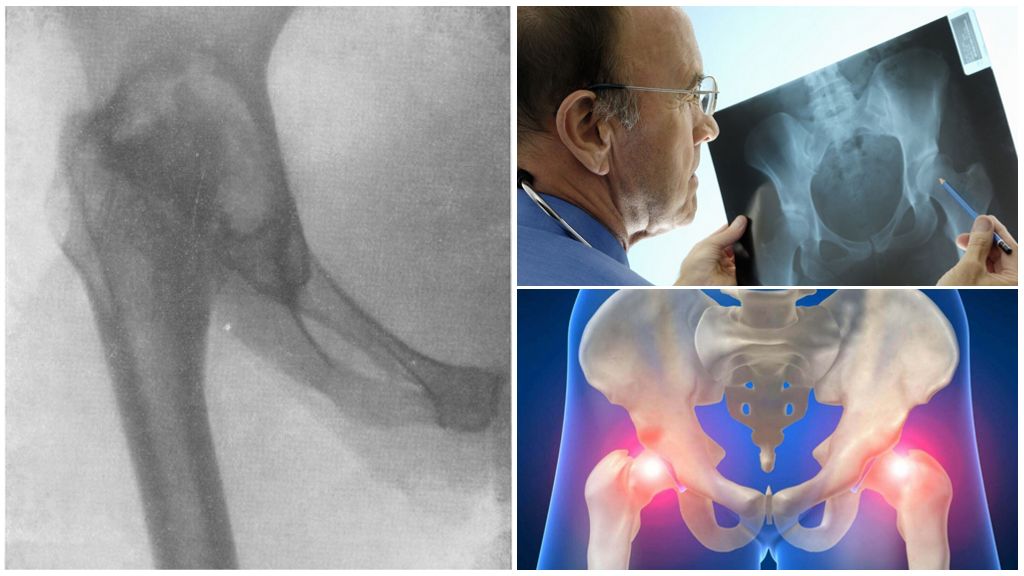

Здоровье суставов: Трохантерит и его влияние на мышцы